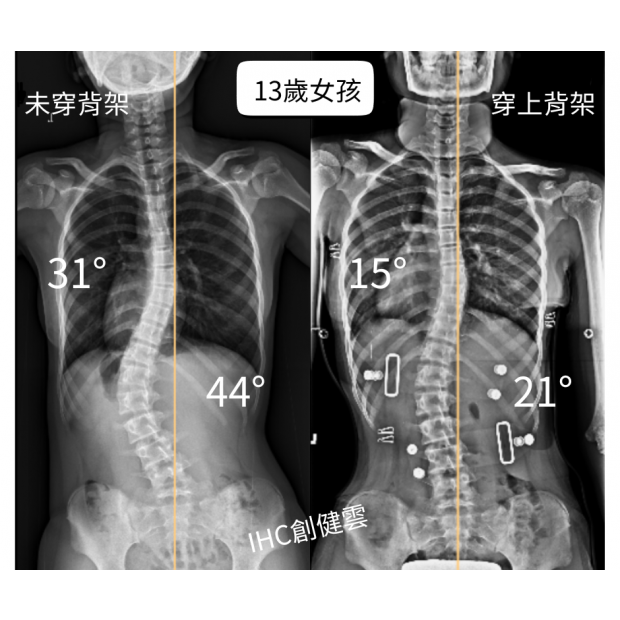

13歲女孩,胸彎31度腰彎44度 穿上背架後立即矯正效果

13歲女孩,胸彎31度腰彎44度